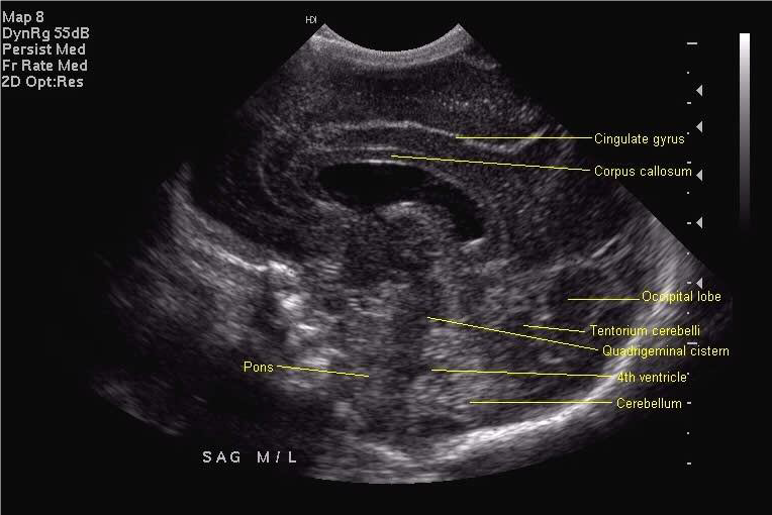

All scan results should be discussed with parents and, unless normal, this should be done by a member of the senior medical team. Although standard views for examination and hard copy print out are shown below, it is good practice to examine the peripheries of the brain including extreme lateral sagittal views, extreme anterior and posterior coronal views.

Midline Sagittal